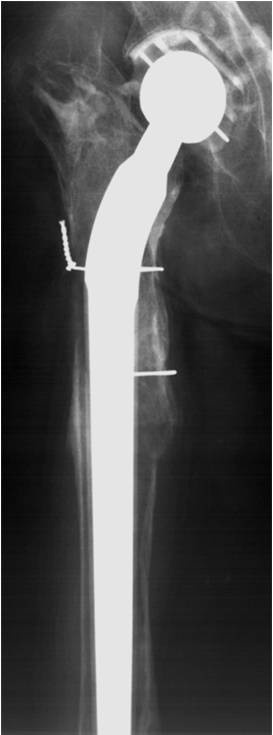

Standardschäfte oder Monoblock-Revisionsschäfte erlauben in nur sehr begrenztem Umfang die Adaptation an diese Bedingungen. Sie erfordern in der Regel eine distale Fixierung, ermöglichen nur eine inkomplette Füllung der Defekte, Offset und Anteversion sind nicht variabel und die Beinlängenadaptation limitiert (Abb. 1a, b).